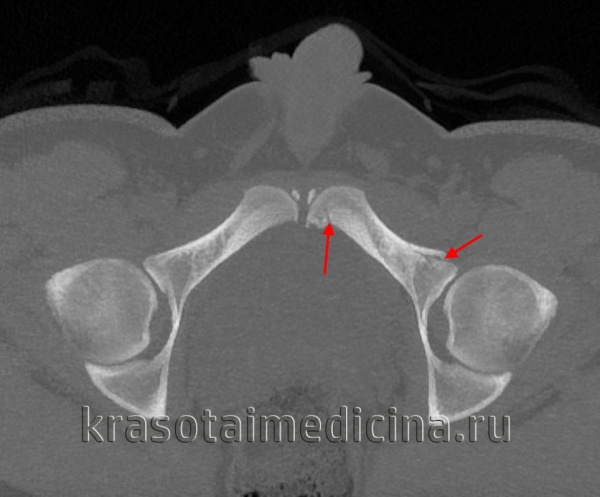

(Слева) КТ у мужчины 19 лет, упавшего с высоты 6 метров и приземлившегося на бок, аксиальный срез. Определяется вколоченный перелом через вторую зону крыла крестца слева, что указывает на травму по типу ла -теральной компрессии. Перелом со смещением правого крестцово-подвздошного сочленения указывает на передне-заднее направление приложения силы по отношению к правой половине таза. Это нестабильный таз, ЛК III.

(Справа) КТ, коронарный срез: у этого же пациента определяется вколоченный перелом крестца слева и полный разрыв крестцово-подвздошного сочленения справа вследствие передне-заднего направления приложения силы. ЛК III встречаются редко. (Слева) При рентгенографии в передне-задней проекции у мужчины 35 лет определяется травма по типу ВТ. Левое крестцово-подвздошное сочленение полностью разорвано, левая половина таза смещена кверху, а также отмечаются переломы лобковой кости справа и подвздошной кости слева. Крестцово-подвздошное сочленение справа расширено спереди.